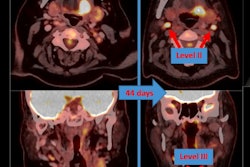

Indeterminate lesion on PET/CT classified by PET/MRI for 53-year-old man with lung cancer. Contrast-enhanced CT (A), PET (B), and fused F-18 FDG PET/CT (C) images are displayed in comparison with contrast-enhanced T1-weighted MRI (D), PET (E), and fused F-18 FDG PET/MRI (F) images. In CT (A), hyperdense, subcentimeter liver lesion (arrows) in segment VII is suggestive of transient hepatic attenuation difference or small hemangioma. As malignancy cannot be excluded, it needs further investigation. On PET/MRI, lesion is clearly classified as metastasis because of contrast enhancement and tracer uptake due to later acquisition time point. Follow-up CT confirmed diagnosis after 78 days. Image courtesy of the Journal of Nuclear Medicine.After exclusions, the researchers examined 1,003 PET/MRI scans of 918 patients. PET/MRI outperformed PET/CT in terms of providing more tumor information (26.3%), mostly in patients with malignant bone disease, followed by lung cancer, prostate cancer, and gynecologic or breast cancer. PET/MRI identified additional malignant findings in 5.3% of cases, which lead to a change in tumor, node, and metastases (TNM) staging in 2.9% of cases. PET/MRI also clearly classified indeterminate PET/CT lesions in 11% of cases.

A smaller percentage of lesions, 2.9%, were detected on PET/CT but not visible on PET/MRI. Of those lesions, 1.2% were malignant and led to a change in TNM staging in 0.5%. It should be noted PET/MRI missed a negligibly small number (0.8%) of lung metastases, which contradicts previous beliefs that the chest requires additional CT, the authors wrote. In addition, new MRI sequences such as ultrashort echo-time sequences are expected to improve lung nodule detection, which would also enhance the sensitivity of PET/MRI even further, they added.